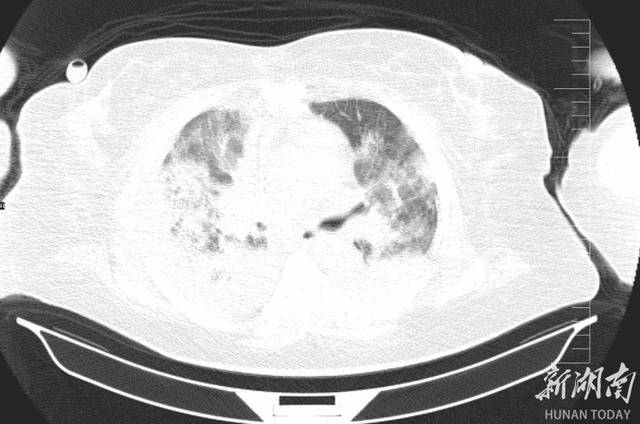

2025 年 12 月 24 日,李阿姨被紧急送入郴州市宜章县人民医院 ICU,她高烧不退、呼吸困难,CT片子上双肺几乎全白了 —— 这是重症肺炎最凶险的信号之一。更麻烦的是,她本身还有肝硬化腹水、十二指肠溃疡大出血等一堆老毛病,所有问题撞在一起,性命危在旦夕。面对如此凶险的病情,救治刻不容缓,ICU 团队火速完成检查并召集多学科会诊,病因被精准锁定:鹦鹉热衣原体感染。

肺部CT可见,重症肺炎较之前大部分被吸收